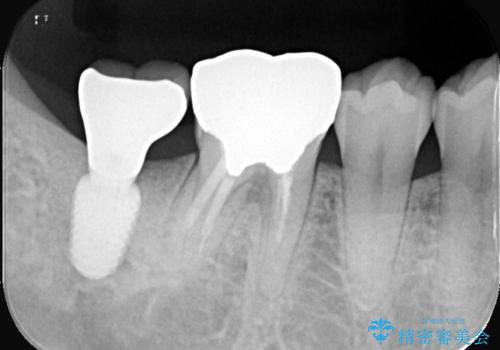

- 患者様は、奥歯を失ったことで「しっかり噛めるようになりたい」とのご希望で来院されました。ブリッジや入れ歯ではなく、インプラントによる治療を希望されたため、精密検査を実施。骨の状態が良好であったため、1回法(1回の手術でインプラント埋入とヒーリングアバットメント装着を同時に行う方法)を選択しました。これにより、外科的負担を軽減しながら、治療期間の短縮も図ることができました。

手術は1回で完了し、局所麻酔下でインプラントを埋入した後、ヒーリングアバットメントを装着。術後の腫れや痛みも少なく、患者様はスムーズに日常生活へ戻ることができました。約3ヶ月の治癒期間を経て、セラミッククラウンをセット。見た目の美しさはもちろん、天然歯に近い噛み心地を実現しました。患者様からは「違和感なくしっかり噛める」とご満足の声をいただきました。